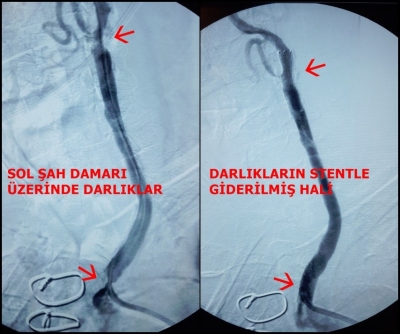

MEMLEKET GİBİSİ OLMAZ DEDİLER FRANSA’DAN DENİZLİ TEKDEN HASTANESİ’NE GELDİLER

ŞAH DAMARI TIKALIYDI, AMELİYATSIZ KURTULDU